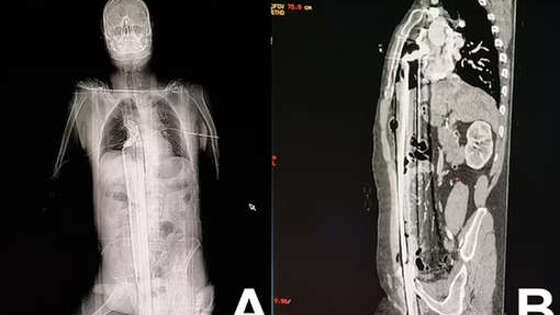

В Бразилии мужчина выжил после страшного инцидента на стройке: он упал с высоты пяти метров на железный прут. Об этом сообщает Daily Mail. Инцидент произошел на стройплощадке в городе Куритиба: 57-летний рабочий находился на строительных лесах, когда поскользнулся и полетел вниз. Падение пришлось на торчавший металлический штырь, который пронзил мужчину вдоль: штырь вошел через пах, поразил печень и достиг верхней части диафрагмы, едва не задев сердце. Мужчину на скорой доставили в больницу, где врачи по частям достали из него штырь, зашили раны и сделали переливание крови. Через два дня пациента перевели из реанимации в общую палату: к этому моменту он самостоятельно передвигался и принимал пищу. Пациента выписали на 12-й день, позже ему провели операцию, чтобы восстановить поврежденную часть уретры, на которой образовался рубец.